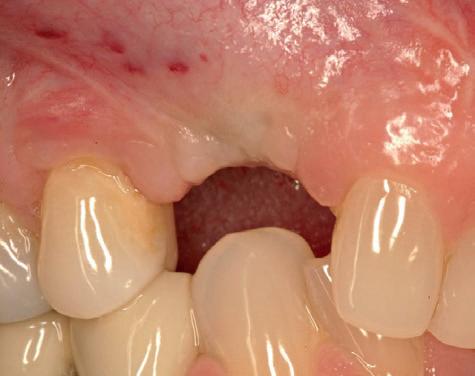

Twee weken later zie ik de patiënt terug voor controle van de eerste wondgenezing. De noodprothese mag de eerste twee weken niet gedragen worden en wordt tijdens de controle zorgvuldig aangepast aan de nieuwe situatie. Hiervoor wordt de prothese gedeeltelijk uitgefreesd en voorzien van een Soft Reliner materiaal. Te veel druk op de beide kaken moet ten alle tijden voorkomen worden en heeft effect op de ingroei van de botopbouw. De genezingsperiode duurt tenminste zes maanden voordat verdergegaan kan worden met de tweede fase: de abutment chirurgie. Hierbij wordt extra aandacht besteed aan het herstel van de gekeratiniseerde gingiva rondom de abutments. Dit komt ten goede aan de uitvoering van de mondhygiëne en dus de stabiliteit van de peri-implantaire mucosa. Deze ogenschijnlijk eenvoudige behandeling is essentieel voor de prognose van de implantaten op de lange termijn. Te weinig gekeratiniseerde mucosa maakt zelfzorg (borstelen/interdentaal reinigen) vaker pijnlijk of lastig, waardoor plaque en mucositis makkelijker kunnen ontstaan en blijven over de lange termijn. Dat kan bij patiënten die vatbaar zijn voor peri-implantitis zich vertalen naar crestaal botverlies rondom implantaten. Gek genoeg wordt de essentie van het herstellen van de gekeratiniseerde gingiva rondom implantaten regelmatig genegeerd.

Herstel van gekeratiniseerde mucosa en weke delenmanagement

De breedte en kwaliteit van de peri-implantaire mucosa beïnvloeden niet alleen esthetiek, maar met name de uitvoerbaarheid van zelfzorg en de stabiliteit van de mucosale barrière. Consensus reports en meta-analyses laten zien dat een beperkte of afwezige col van gekeratiniseerde peri-implantaire mucosa (vaak gedefinieerd als <2 mm) geassocieerd kan zijn met (1) meer plaque-accumulatie, (2) meer wekedelen-inflammatie, (3) meer mucosale recessie, (4) meer marginaal botverlies en (5) een hogere prevalentie van peri-implantitis.4-6 In de dagelijkse praktijk is dit vooral relevant bij full-arch restauraties waarbij de connectie prothese-abutments en de overgang prothese-mucosa moeilijker te reinigen zijn. Bij onvoldoende gekeratiniseerde mucosa of een ondiepe omslagplooi wordt poetsen vaak pijnlijk, waardoor plaquecontrole onvoldoende is en peri-mucositis gemakkelijk ontstaat. Dit verdedigt de indicatie voor een wekedelen augmentatie als chirurgisch onderdeel van de implantologische behandeling. Streefwaarde van ongeveer ≥2 mm gekeratiniseerde mucosa rondom implantaten wordt in de literatuur vaak gehanteerd.4, 5 Technisch kan dit in de tweede fase (abutmentchirurgie) voorafgaand aan de prothetiek worden uitgevoerd met een apicaal gepositioneerde flap, al dan niet gecombineerd met een gesteelde dan wel een vrij bindweefseltransplantaat (free gingival graft, FGG). FGG geldt als ‘standard of care’ voor voorspelbare toename van gekeratiniseerde mucosa. Xenogene collageenmatrixen kunnen in geselecteerde gevallen een alternatief zijn, bijvoorbeeld om donor site morbiditeit te beperken.4 Waar dikte en contour belangrijk zijn (recessies/esthetiek) wordt vaker een bindweefseltransplantaat overwogen.